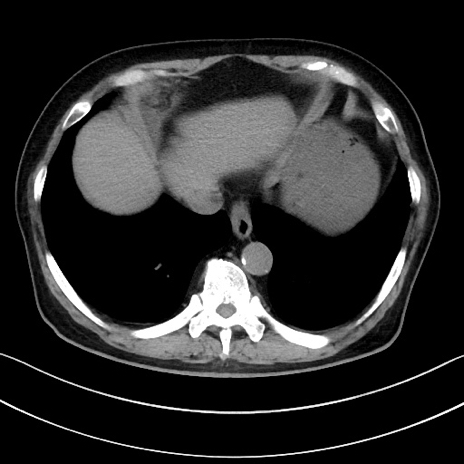

症例15(横断像)

【症例】70歳代男性

【主訴】腹痛

【現病歴】今朝から腹痛あり。全体的に痛い。特に左上の方。排ガスが今日はない。冷や汗が出る。

【既往歴】直腸癌術後

【身体所見】左側腹部〜上腹部に圧痛あり。腹膜刺激症状明らかなではない。軽度反跳痛。左下腹部に術後瘢痕あり。

【データ】WBC 7700、CRP 0.02